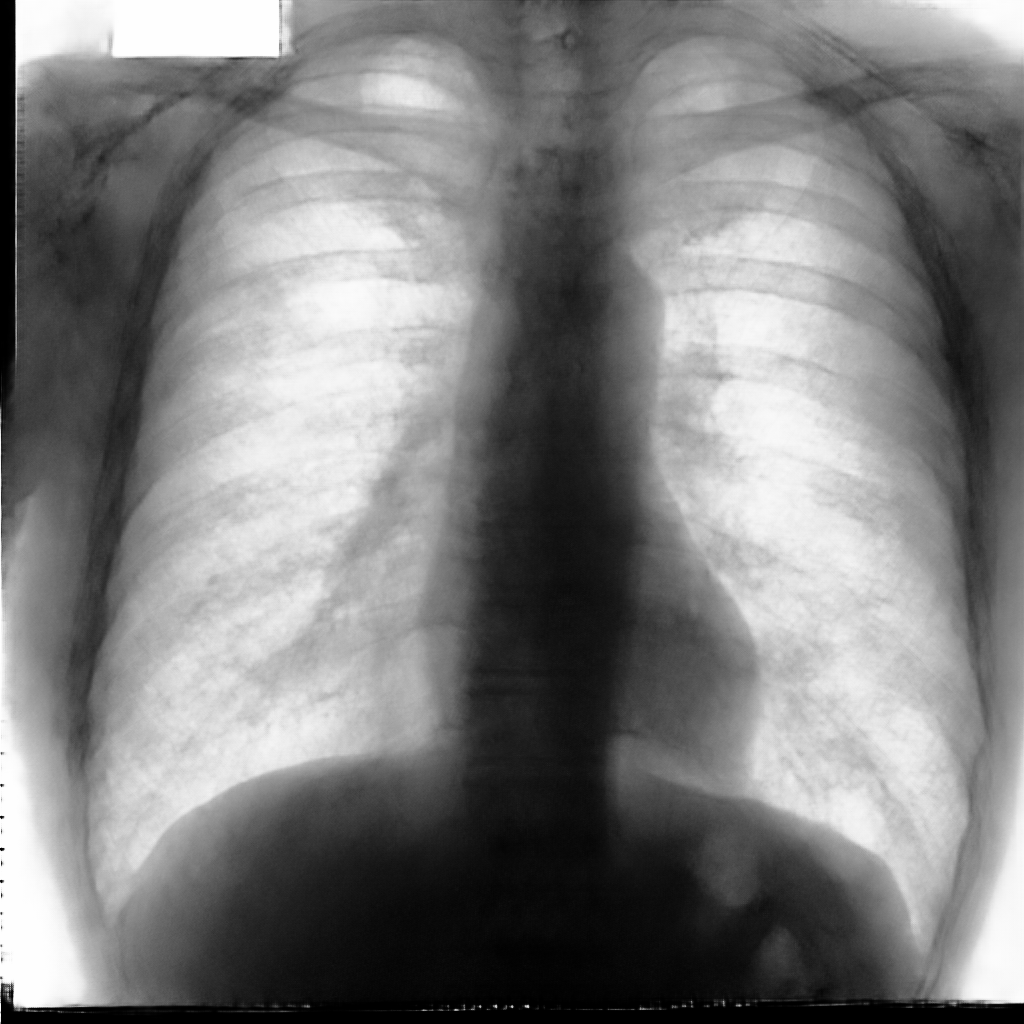

In this section, some examples of images and corresponding segmentations, generated with the approaches described in Section 3, are qualitatively examined. We also report some comments from three physicians on the generated segmentations, to provide a medical assessment of the quality of our method.

Figure 5 and Figure 6 display some examples — randomly chosen from all the generated images — of the label–maps and the corresponding chest X–ray images generated with the three methods described in Section 3, using the FULL_DATASET and the TINY_DATASET, respectively. We can observe that, with the single and two–stage methods, the images tend to be more similar to those belonging to the training set. For example, in most of the generated images there are white rectangles, which resemble those present in the training images, used to cover the names of both the patient and the hospital. Instead, the three–stage method does not produce such artifacts, suggesting that it is less prone to overfitting.

Moreover, in order to clarify the limits of the three–stage method, we assessed the quality of the segmentation results based on three human experts, who were asked to check 20 chest X–ray images, along with the corresponding supervision and the segmentation obtained by the SMANET network. Such images were chosen among those that can be considered difficult, at least based on the high error obtained by the segmentation algorithm. Figure 7 and Figure 8 show different examples of the images evaluated by the experts. The first column represents the chest X–ray image, while the second and the third columns, whose order was randomly exchanged during the presentation to the experts, represent the target segmentation and our prediction, respectively. The three physicians were asked to choose the best segmentation and to comment about their choice. Apart from a general agreement of all the doctors on the good quality of both the target segmentation and the segmentation provided by the three–stage method, surprisingly, they often chose the second one. For the examples in Figure 7, for instance, all the experts share the same opinion, preferring the segmentation obtained by the SMANET over the ground–truth segmentation. To report the results of the qualitative analysis, we numbered the target and predicted segmentation with 1 and 2, respectively, while doctors were assigned unordered pairs to obtain an unbiased result. Then, with respect to Figure 7(a), the comments reported by the experts were: 1) In segmentation 1, a fairly large part of the upper left ventricle is missing; 2) I choose the segmentation number 2 because the heart profile does not protrude to the left of the spine profile; 3) The best is No. 2, the other leaves out a piece of the left free edge of the heart, in the cranial area. Instead, for Figure 7(b), we obtained: 1) The second image is the best for the cardiac profile. For lung profiles, the second image is always better. The only flaw is that it leaks a bit on the right and left costophrenic sinuses. 2) Image 2 is the best, because the lower cardiac margin is lying down and does not protrude from the diaphragmatic dome. Image number 1 has a too flattened profile of the superior cardiac margin. 3) No. 2 for the cardiac profile more faithful to the real contours.

Instead, they reported conflicting opinions or decided not to give a preference with respect to the examples in Figure 8. When they agreed, they generally found different reasons for choosing one segmentation over the other. With respect to Figure 8(a) the comments reported by the experts were: 1) I prefer not to indicate any options because the heart image is completely subverted; 2) Segmentation number 2 is better, even if it is complicated to read because there is a “bottle–shaped” heart. The only thing that can be improved in image 2 is that a small portion of the right side of the heart is lost; 3) No. 1 respects more what could be the real contours of the heart image. Instead, for Figure 8(b) we obtained: 1) I prefer No. 2 because the tip of the heart is well placed on the diaphragm and does not let us see that small wedge–shaped image that incorrectly insinuates itself between heart and diaphragm in image 1 and which has no correspondence in the RX; 2) Both are good segmentations. Both have small problems, for example: in segmentation 1 a small portion of the tip (bottom right of the image) of the heart is missing, in segmentation 2 a part of the outflow cone (the “upper” part of the heart) is missing. It is difficult to choose, probably better No. 1 because of the heart; 3) No. 2 because No. 1 carnally probably exceeds the real dimensions of the cardiac image, including part of the other mediastinal structures.